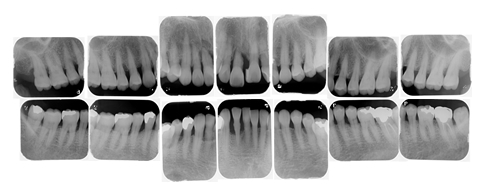

診察・検査

検査には、レントゲン撮影、お口の写真撮影、歯周ポケット、歯の動揺度、プラークのつき方、口臭測定、位相差顕微鏡検査などを行います。

- 14枚法

- 全ての歯の骨吸収状態をくわしく確認できるように、14枚のレントゲンに分けて細かく撮影し、精密な診断を行なっていきます。